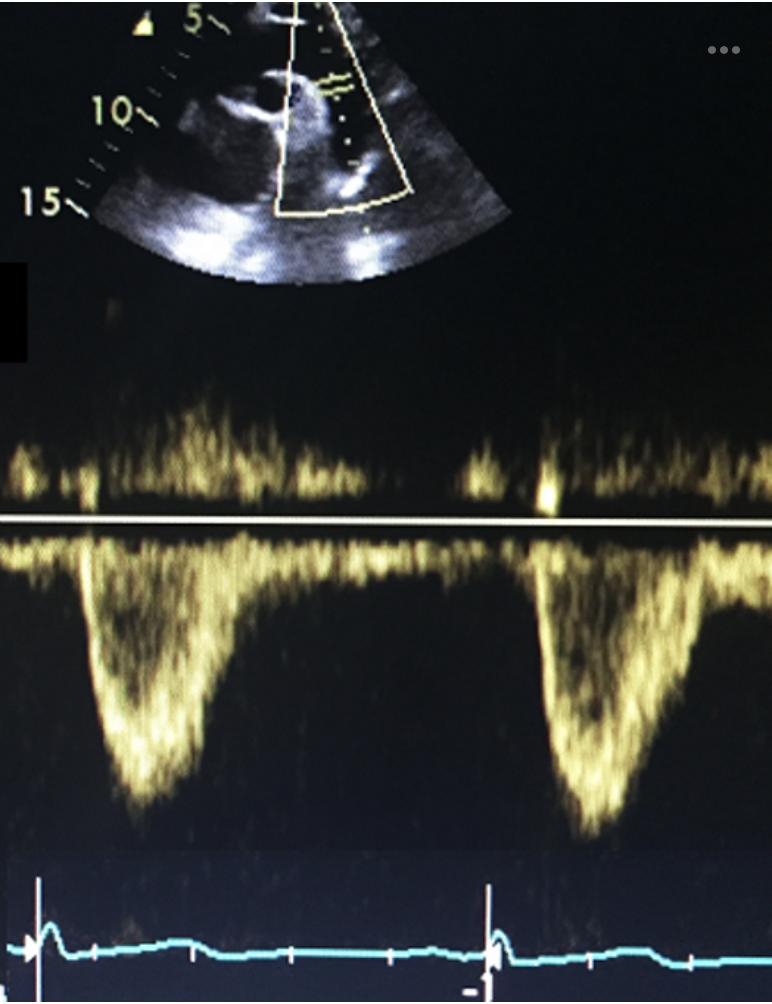

Q

What structure is being identified at the yellow arrow in this apical 4 chamber view of the right heart?

a) foramen ovale

b) SVC

c) coronary sinus

d) eustacian valve

A